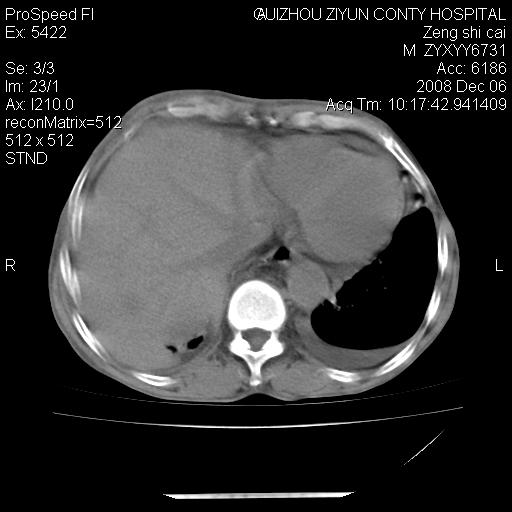

标题: CT16961:M、71岁,咳嗽半年,无血痰;胸片示右肺占位。 [打印本页]

标题: CT16961:M、71岁,咳嗽半年,无血痰;胸片示右肺占位。

升结肠癌伴腹膜后淋巴结转移

右肺癌并纵隔淋巴转移,腹膜后转移可能性大,两侧胸腔积液

1)考虑右肺上叶纵隔型肺癌伴纵隔淋巴结转移。2)心包积液,双侧胸腔积液。